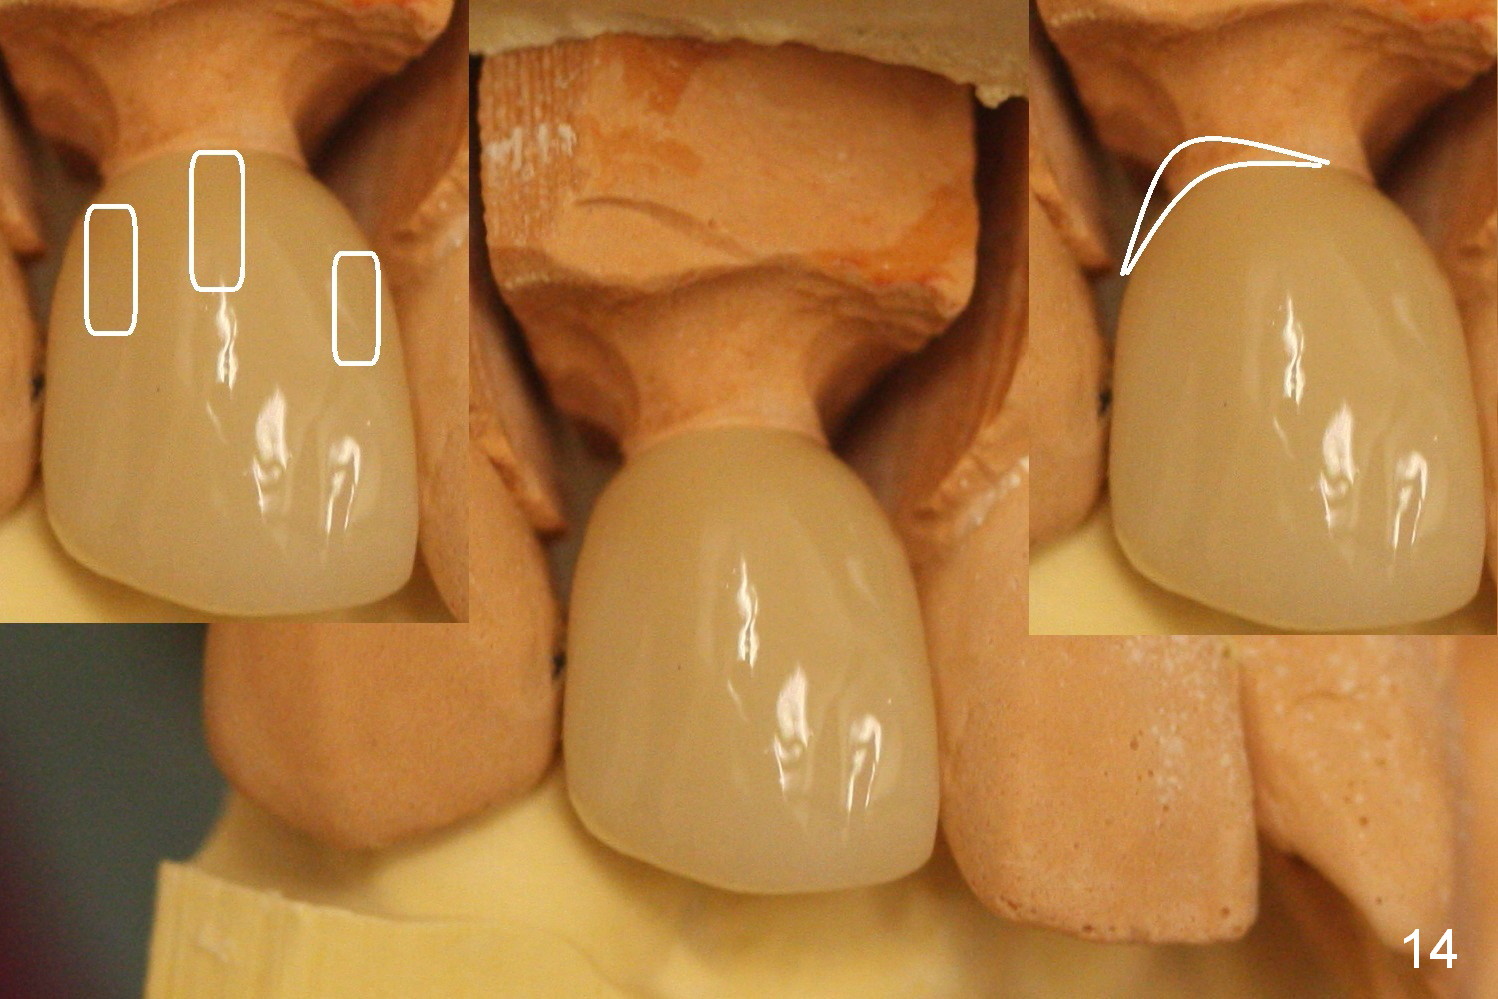

In fact the abutment margin is flat (Fig.13, not trimmed as shown in the inset). To avoid excess cement, cement is applied short of the mesial margin inside the crown (Fig.14 left inset (white area)). Once the crown is seated with cement, the excess one is present anywhere other than the mesial (Fig.14 right inset (white area)).